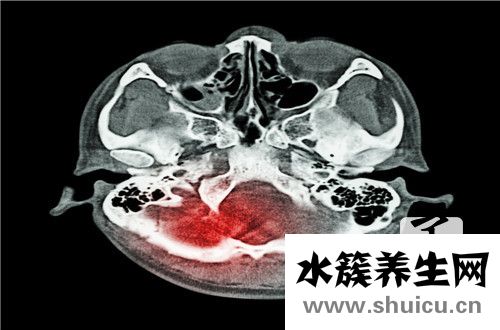

很多人在日常生活中都遇到過骨折的問題,骨折的情況相當多,有的是大腿骨折,手關節骨折,手指骨折。顱中窩骨折很多人聞所未聞。這種骨折會導致流鼻血,甚至各種裂縫和損傷,甚至嚴重的可能導致耳流。...